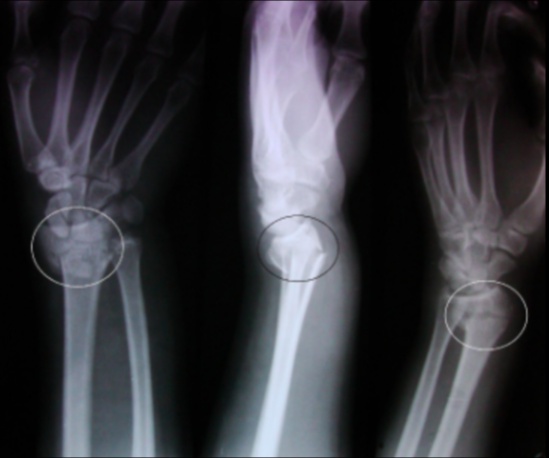

Colles

A dorsally displaced distal radius fracture

Typically the result of a fall on an out-stretched hand (FOOSH) that is in dorsiflexion. Compare this to a Smith’s fracture, which occurs after a fall on an outstretched hand that is in volar flexion.

A Colles’ fracture presents with tenderness and swelling at the distal forearm with or without visible deformity.

Treatment of a Colles’ fracture consists of:

Closed reduction and casting if stable

Closed reduction with percutaneous pinning if unstable

Open reduction with internal fixation if unstable.

Smith

A volar displaced distal radius fracture.

Typically the result of a fall on an out-stretched hand that is in volar flexion., opposite of the dorsiflexion that produces a Colles’ fracture. They are much less common than a Colles’ fracture.

A Smith’s fracture presents with tenderness and swelling at the distal forearm with or without visible deformity, similar to Colles’ fracture.

Treatment of a Smith’s fracture consists of:

Open reduction with internal fixation if unstable